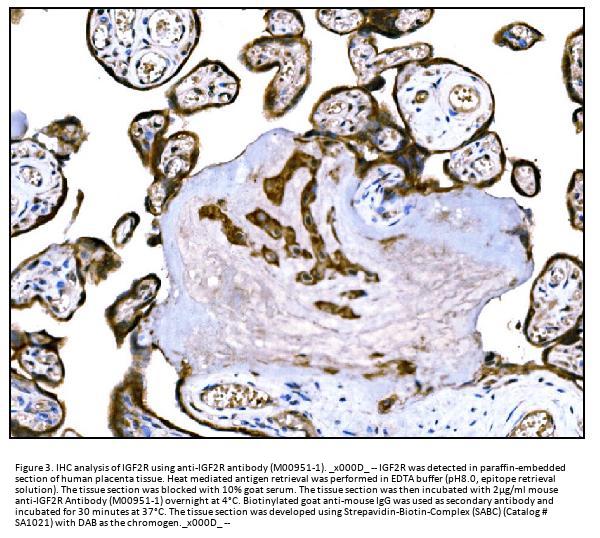

Immunohistochemistry (Paraffin-embedded Section), 2-5μg/ml, Human

E. coli-derived human IGF2R recombinant protein (Position: F424-R529).